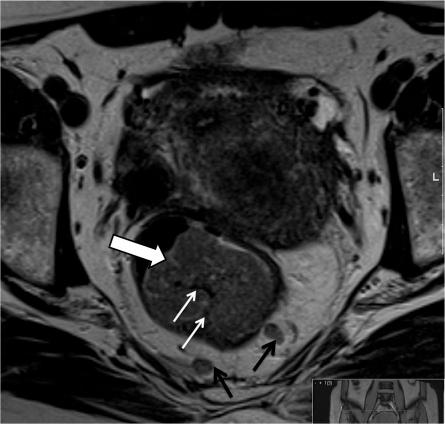

基于表格的直肠癌报告。

Proforma-based reporting in rectal cancer.

The improvements in outcomes associate with the use of preoperative therapy rather than postoperative treatment means that clinical teams are increasingly reliant on imaging to identify high-risk features of disease to determine treatment plans. For many solid tumours, including rectal cancer, validated techniques have emerged in identifying prognostic factors pre-operatively. In the MERCURY study, a standardised scanning technique and the use of reporting proformas enabled consistently accurate assessment and documentation of the prognostic factors. This is now an essential tool to enable our clinical colleagues to make treatment decisions. In this review, we describe the proforma-based reporting tool that enables a systematic approach to the interpretation of the magnetic resonance images, thereby enabling all the clinically relevant features to be adequately assessed.

摘要

术前治疗而非术后治疗带来的结果改善意味着临床团队越来越依赖于影像学来识别疾病的高危特征以确定治疗方案。对于许多实体瘤,包括直肠癌,已经出现了用于术前识别预后因素的验证技术。在 MERCURY 研究中,标准化的扫描技术和报告表格的使用使得对预后因素的准确评估和记录成为可能。这现在是我们的临床同事做出治疗决策的重要工具。在这篇综述中,我们描述了基于报告表格的报告工具,它使我们能够对磁共振图像进行系统的解读,从而能够充分评估所有与临床相关的特征。